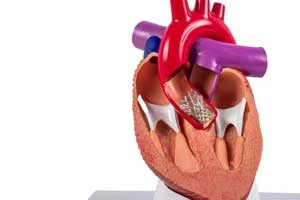

Valve Replacement Surgery

Replacement of damaged heart valves with artificial valves

Valve Replacement Surgery

Replacement of damaged heart valves with artificial valves